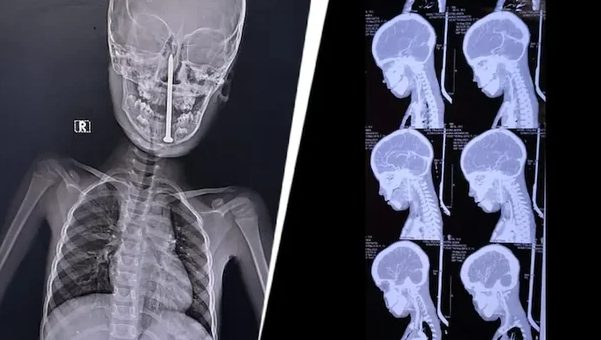

7세 남자아이가 놀던 중 넘어지면서 목을 통해 8cm 길이의 못이 뇌까지 박히는 사고가 발생했다.

의료진이 실시한 MRI와 CT 검사 결과, 못이 뇌의 민감한 부위를 관통한 사실이 확인되자 신경외과, 이비인후과, 마취과, 소아과, 외상외과 등 전문 의료진이 긴급 소집됐다.

10시간에 걸친 대수술은 최첨단 미세수술 기법과 신경 내비게이션 시스템까지 동원돼 진행됐으며, 중요한 혈관이나 뇌 기능의 손상 없이 못이 제거됐다.